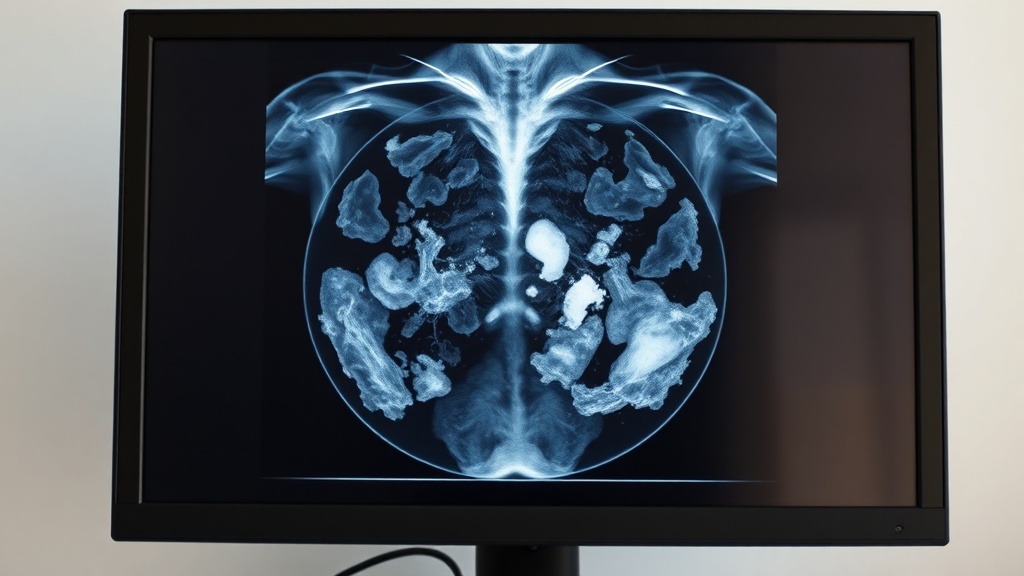

A routine mammogram recently led to an early-stage breast cancer diagnosis for Sarah Walton, a 53-year-old resident of Bingley. Ms. Walton expressed her shock at the diagnosis, particularly because she has no family history of the disease and could not feel any lumps.